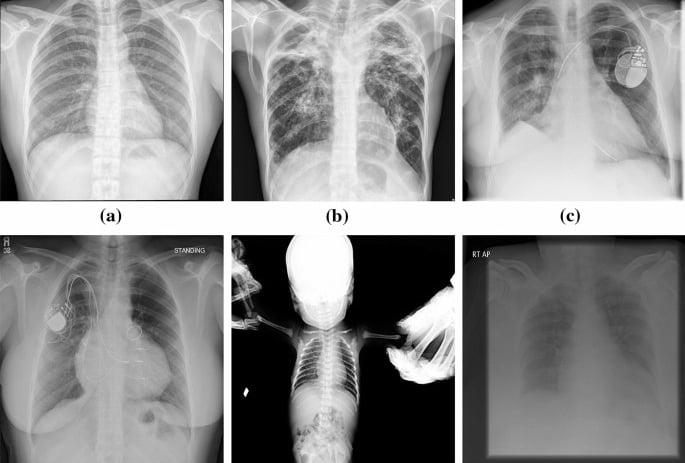

a. Start by Examining the Quality of the Image

Before diving into specifics, you need to evaluate the quality of the X-ray image. An unclear or poorly exposed X-ray can make it difficult to see the details necessary for accurate interpretation. Check for:

Proper exposure: Are all areas of interest clear and visible?

Good positioning: Is the patient’s body positioned correctly for the X-ray?

No motion blur: Is the image sharp, or does it look fuzzy due to patient movement?

d. Evaluate the Lungs and Heart (in Chest X-Rays)

A chest X-ray typically includes the lungs and heart. Here’s what to look for:

Lungs: Check the lungs for any abnormal spots, shadows, or consolidations (which might indicate infection like pneumonia or other lung conditions).

Heart: Ensure that the heart’s size and shape appear normal. Enlargement or abnormalities could indicate conditions such as heart failure or pericardial disease.

e. Consider the Positioning and Symmetry

Always keep in mind the positioning of the X-ray. Is the body aligned properly? In a PA (posteroanterior) chest X-ray, for instance, you would want the patient’s chest to be in an upright position to avoid distortion. Compare both sides of the body, especially if it’s a full-body X-ray, to identify any asymmetry or abnormalities.